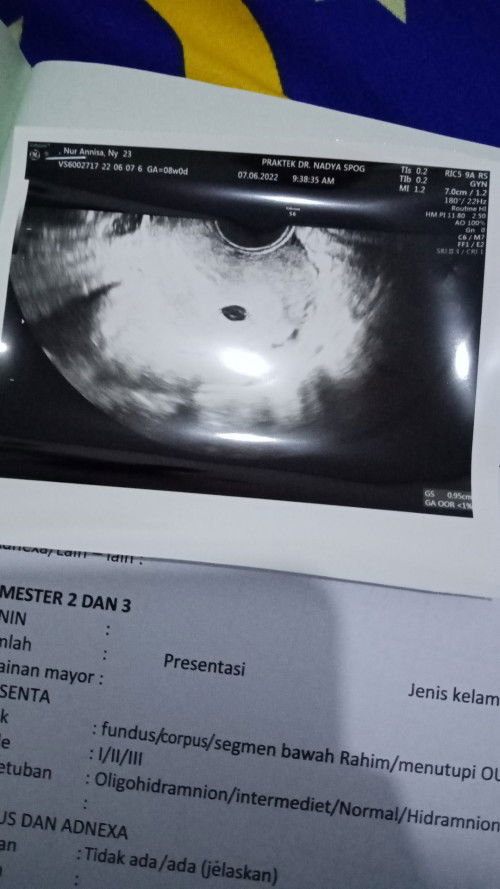

8week kantung janin kecil

hari ini tepat usia kehamilan aku 8week dan memutuskan untuk USG transvagina. janinku di vonic tidak berkembang karna tidak sesuai usia kehamilan aku saat ini😭 bunda2 ada ngga yg pengalamannya kaya aku?? apa solusinya?? #8week#kantungjanin